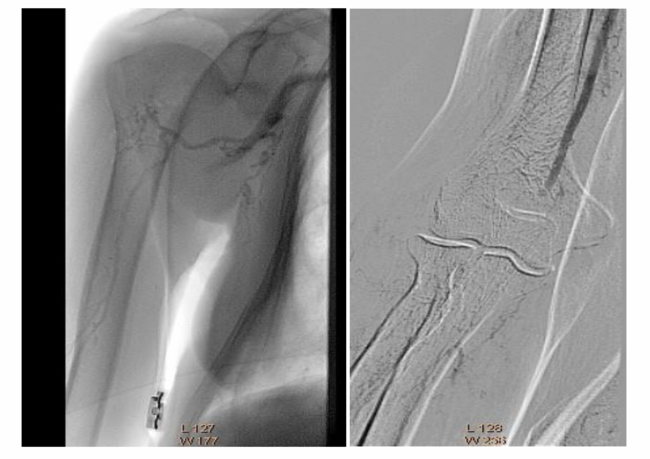

The angiography was performed via the left common femoral artery. The diagnostic catheterization of the right upper limb showed a thrombus in the origin of the right brachial artery, second level of thrombosis in the brachial bifurcation into its ulnar and radial branches, and poor distal filling of the radial artery (Figure 1).